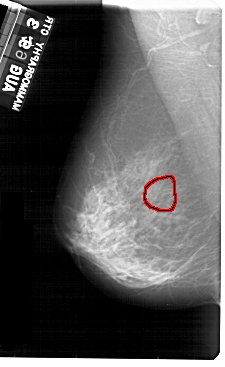

A_1954_1.LEFT_MLO

LEFT_MLO LINES 5491 PIXELS_PER_LINE 3361 BITS_PER_PIXEL 12 RESOLUTION 43.5 OVERLAY

FILE: A_1954_1.LEFT_MLO.OVERLAY

TOTAL_ABNORMALITIES 1

ABNORMALITY 1

LESION_TYPE CALCIFICATION TYPE PUNCTATE DISTRIBUTION CLUSTERED

ASSESSMENT 4

SUBTLETY 3

PATHOLOGY BENIGN

TOTAL_OUTLINES 1

BOUNDARY